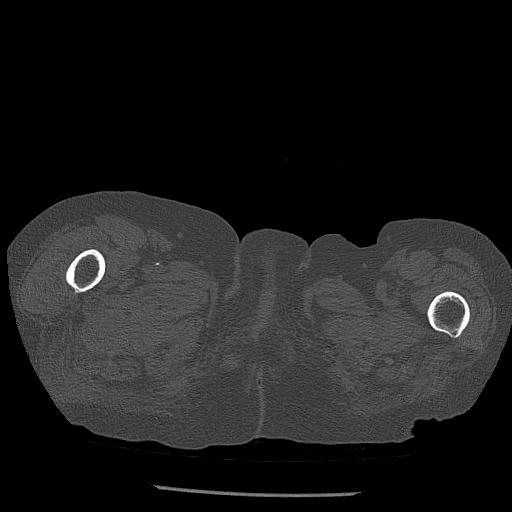

56476 8/28 4R 1/21 2R 左足関節 デジカメ写真 72歳女性 右足関節AS